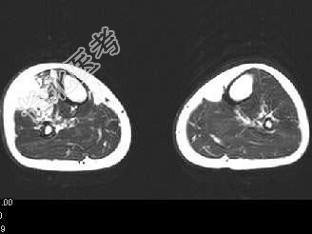

- 单项选择题男,15岁, 小时候发现左下肢肿胀,曾多次出血, 结合图像,最可能的诊断是 ( )

C、下肢血管瘤